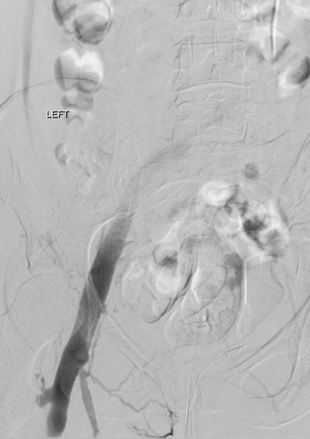

Vista de posición decúbito prono de trombo agudo en la vena femoral común izquierda y ausencia de flujo en las venas ilíacas.

Vista de posición decúbito prono de la pierna izquierda tras la trombectomía mediante el catéter DVX de AngioJet utilizando la técnica Rapid Lysis (25 mg de tPa en 250 cc de solución salina natural). Desaparición del trombo, oclusión subyacente de la vena ilíaca común izquierda revelada.